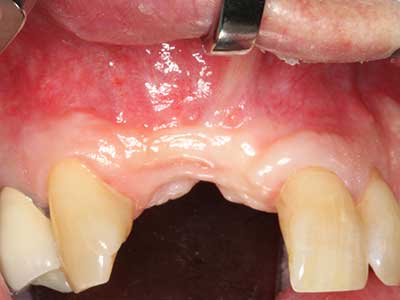

En la extracción de bloques óseos la piezocirugía también presenta ventajas adicionales: Además de la alta precisión en la osteotomía que ya se ha descrito antes, se ha comprobado que el uso de los delgados insertos de sierra resulta especialmente cuidadosas con el hueso. Frente a esto, sobre todo cuando se usan las fresas de Lindemann, cabe esperar pérdidas en la extracción significativamente más altas debido al mayor grosor de la parte frontal del cabezal (Lakshmiganthan, Gokulanathan et al. 2012). La separación basal que se necesita en particular en los injertos de bloque extraídos de forma retromolar se ve facilitada mediante sierras perpendiculares especialmente previstas a tal fin, lo que permite considerar que la cirugía piezoeléctrica es un procedimiento preciso y seguro para la obtención de bloques de hueso en el área retromolar (Happe 2007) (fig. 1-12).